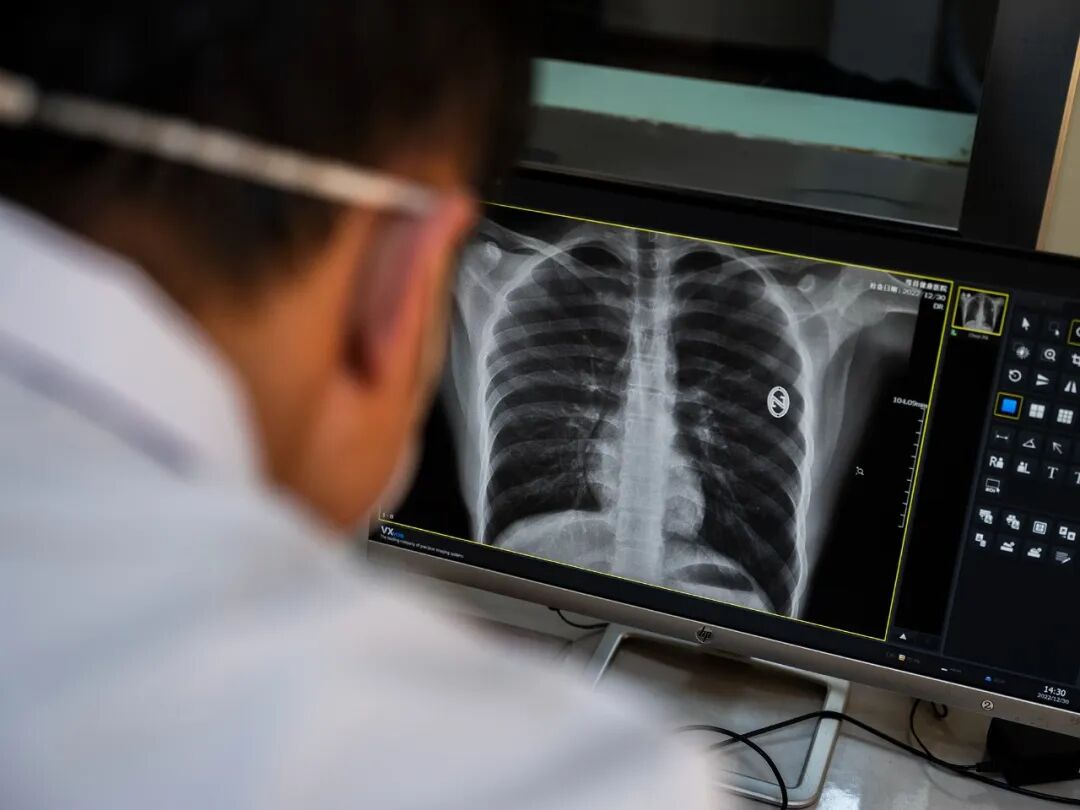

●在工作台前,侯俊在检测患者CT。

●侯俊在看患者的CT。

12月31日中午,影像科走廊依然排满了等着做CT的病人。办公室里,医生侯俊正在为一位73岁的患者写检测报告——“双肺见磨玻璃状高密度影”。侯俊顾不上吃午饭,上午四个小时的工作时间里,科室为患者做了63个CT检查,其中50个是检查肺部的,这是平日里影像科3天的工作量。

从12月24号起,医院迎来看病高峰,每天影像科做的CT检测要在100个以上,多数患者是周边村镇的老人。侯俊统计,从胸部CT显示结果看,肺部有不同程度感染的患者达到80%,65岁以上老人居多。一些老人最初的症状较轻,觉得能扛过去就扛,持续发烧、咳嗽才会到医院,但那时肺部已经出现问题。